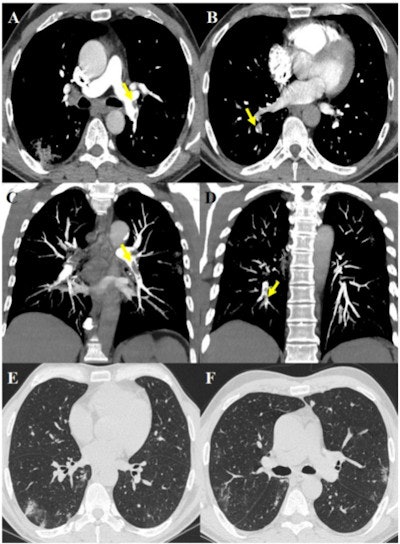

63-year-old male after 17 days of hospitalization without respiratory support and sudden increase of D-dimer value. The images show pulmonary thromboembolism in the lobar arteries for the left lower lobe (yellow arrow, A) and in the segmental arteries for the right lower lobe (yellow arrows, B), confirmed by maximum intensity projection reconstructions (yellow arrows, C and D). Lung parenchyma is characterized by some peripheral subpleural bilateral ground-glass opacities and consolidations (E, F). Images and caption courtesy of the RSNA.The study results may suggest that proactive anticoagulant treatment could be effective for patients with COVID-19, the investigators wrote.

The authors found that 40.6% of patients had PTE and that in most patients, the condition manifested bilaterally or only on the right (90.2%), involved segmental (90.2%) or subsegmental (61%) arteries, and affected mainly lower lung lobes (73.2%).

Of the arteries with PTE, 67.6% showed a consolidation pattern; deep vein thrombosis was identified in only 12.2% of patients. The researchers did not find significant differences between patients with PTE and those without when it came to age, gender, symptoms, comorbidities, tumor history, use of respiratory supports, or the presence of deep vein thrombosis, but they did find statistically significant differences between the groups regarding CT lesion scores and D-dimer, lactate dehydrogenase, and C-reactive protein values: Those with higher scores had more severe disease.